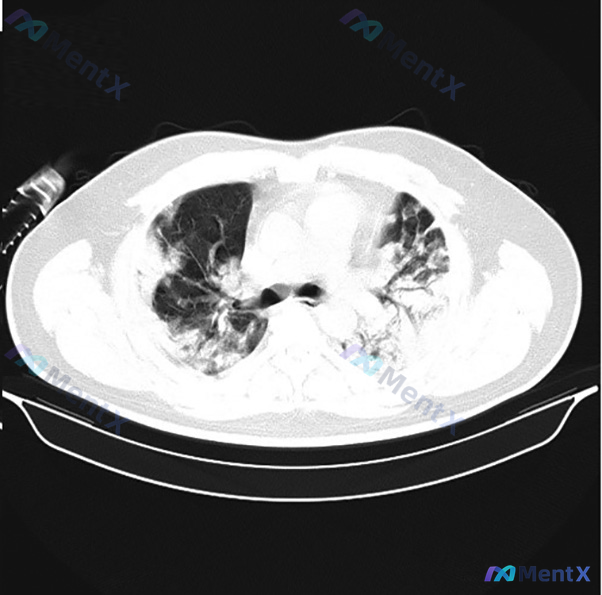

这份双肺弥漫性实变+磨玻璃影的CT,第一反应真的是重症肺炎吗?

整理到一份胸部CT肺窗横断面的影像分析资料,先不放后续临床和实验室结果,仅看影像表现: 核心影像异常: - 双肺广泛分布异常密度影,多灶性、以肺门周围及下肺更显著 - 大片状实变影,内部伴明显支气管充气征 - 实变周边及其他区域可见磨玻璃影,混合存在 - 磨玻璃背景下可见小叶间隔增厚、网格状影 -...